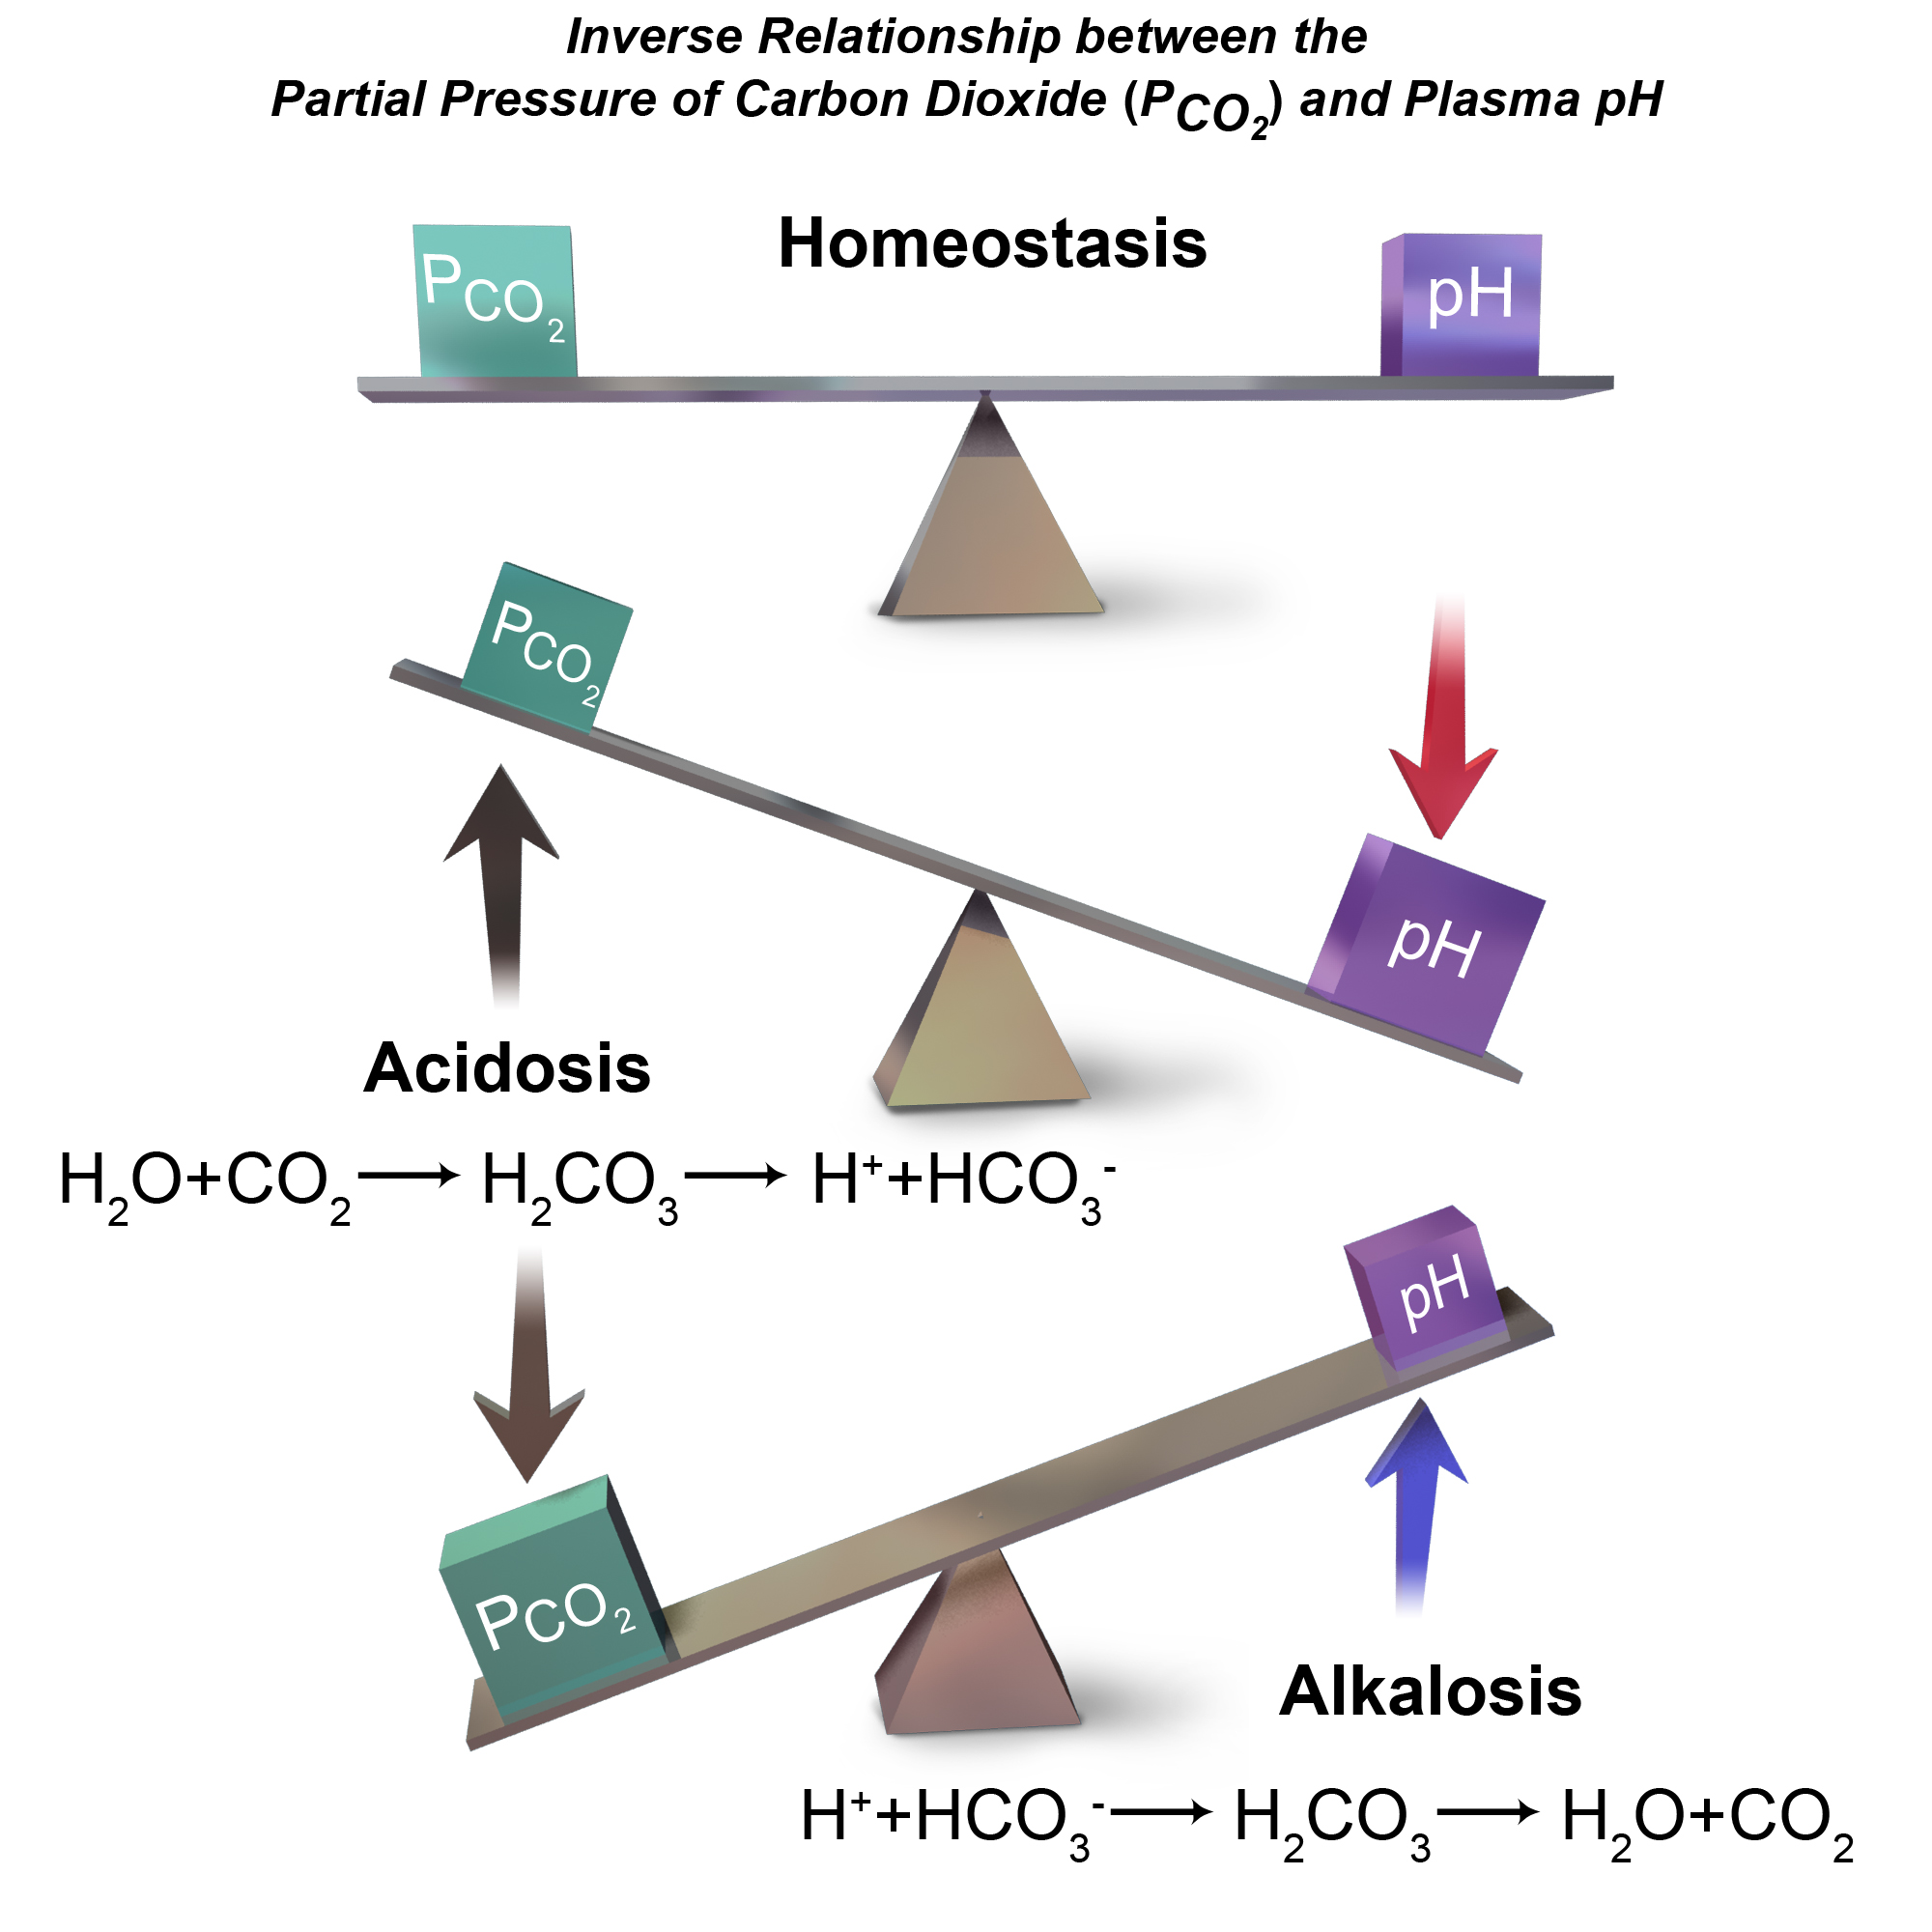

Hypercapnea – is also known as hypercarbia. It is a condition related to high carbon dioxide levels in the body. Carbon-dioxide can get built up in the blood if the body doesn’t successfully get rid of it within time. Conditions that either increase the levels of carbon-dioxide in the body or prevent the waste carbon-dioxide from getting to the lungs and discarded are usually the main causes of hypercapnea. Illnesses related to lung, brain, muscles and nerves are usually the most common causes. Hypercapnia is different to hypoxemia as hypercapnia is the condition with high carbon-dioxide levels in blood whereas hypoxemia is low oxygen levels in blood.

Respiratory failure is a critical condition that develops due to low blood-oxygen levels in the bloodstream that makes involuntary tasks like breathing almost impossible to do on your own. The low blood-oxygen levels results due to inadequate gas exchange during pulmonary circulation, which could be because of pump failure or lung failure. Pump failure is a ventilation failure which causes hypercapnia whereas lung failure is gas exchange failure causing hypoxemia. It can also de defined as arterial oxygen tension (Pao2 < 60mmHg) or arterial carbon dioxide tension (PaCO2).

Type II: – involves alveolar hypoventilation resulting in hypercapnia (PaCO2). There is a significant reduction in the alveolar minute ventilation that entails inadequate removal of carbon dioxide.

Acute respiratory failure vs chronic respiratory failure: In type II respiratory failures, there is active vs chronic respiratory failure, active failure matures and progress over minutes to a couple days and involves respiratory acidosis (a condition where lungs are not able to get rid of all the carbon dioxide in the body). On the contrary, chronic failure takes anywhere from days to months to develop and involves a higher PaCO2 including increased levels of serum bicarbonate due to renal compensation.